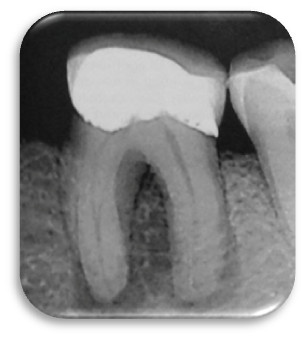

Wskaż prawdziwe stwierdzenie dotyczące załączonego zdjęcia: